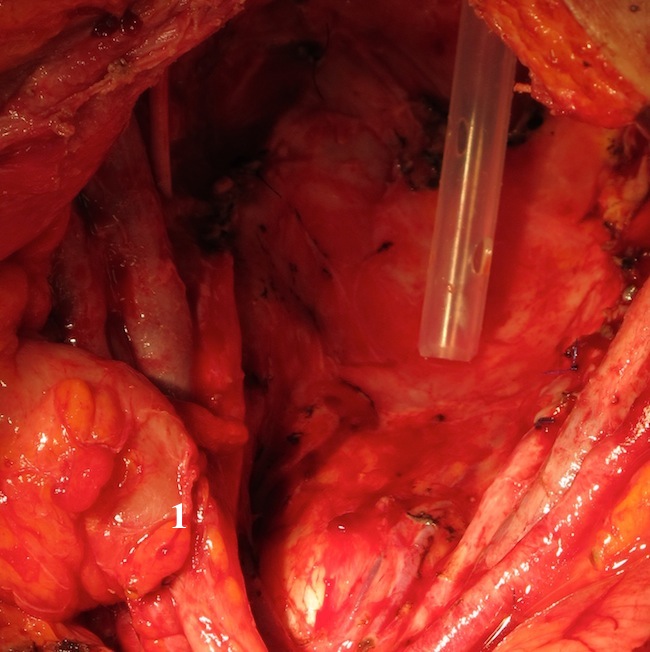

Выполнена резекция вовлеченной в конгломерат подвздошной кишки. Мочеточники визуализированы с обеих сторон, взяты на держалки и пересечены. Мочеточники интубированы катетерами № 9 Ch. Разрез брюшины продлен до корня брыжейки поперечной ободочной кишки. Произведена диссекция клетчатки с лимфатическими узлами вдоль аорты и нижней полой вены от почечных сосудов до парааортальные лимфатические узлы, удалены. Пересечен дистальный конец двуствольной колостомы. Прямая кишка со значительными техническими сложностями мобилизована в малом тазу до диафрагмы таза. Переднебоковые связки ее пересечены. Выделена внебрюшинная часть мочевого пузыря. Пресечена уретра, передняя и задняя стенка влагалища. Уретра, влагалище ушиты Z-образными швами.

Прямая кишка на уровне нижнеампуляного отдела прошита и пересечена. Препарат, включающий влагалище, сегмент подвздошной кишки, сегмент толстой кишки, мочевой пузырь, клетчатку из области подвздошных сосудов, запирательных ямок удален. Сформирован анастомоз подвздошной кишки по типу "конец-в-конец". Контроль проходимости анастомоза. Дефект брыжейки ушит с обеих сторон. Выполнена аппендэктомия. В дистальную изолированную часть сигмовидной кишки с формированием единой площадки имплантированы мочеточники, вместе с проксимальным отделом сигмовидной кишки, выведены в левую подвздошную область.